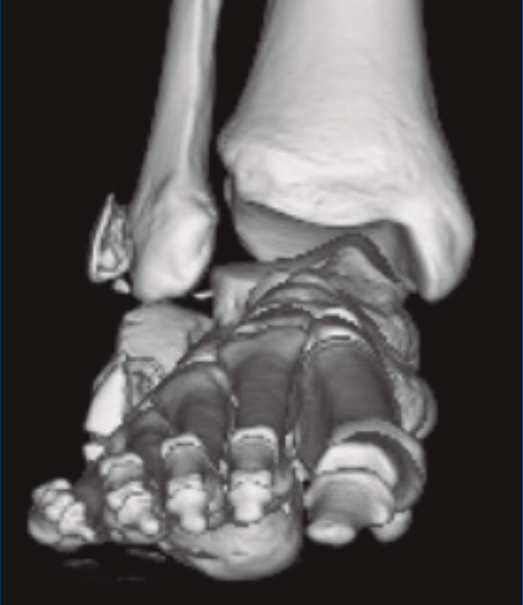

Figura 1. Luxación del astrágalo en mortaja tibioperonea, fractura maléolo peroneo y espacio subperoneo ocupado por calcáneo.

Figura 2. Fractura maléolo peroneo y tibial posterior. Trazo entre fragmento anteromedial y posterolateral.

Figura 3. Desplazamiento entre fragmento anteromedial (sustentaculum tali) y posterolateral (tuberosidad).

Se trata de un varón de 19 años que ingresa en reanimación tras precipitarse desde una altura de aproximadamente 10 metros. El paciente presenta una fractura estallido de L3 con afectación del canal medular junto con una fractura del vértice inferior de L4, así como una fractura luxación de calcáneo, asociada a una fractura del maléolo peroneo y del maléolo tibial posterior (Figuras 1 a 6) diagnosticadas mediante TC total body (por eso no se dispone de radiografías simples al momento del ingreso). Como podemos comprobar, se trata de una fractura de doble trazo de tipo hundimiento/depresión de la carilla articular (Figuras 5 y 6).

Figura 4. Luxación fragmento posterolateral.

Figura 5. Fractura maléolo peroneo, luxación astrágalo, fractura de doble trazo en calcáneo.

Figura 6. Fractura de doble trazo; se evidencia afectación de la articulación calcaneocuboidea.